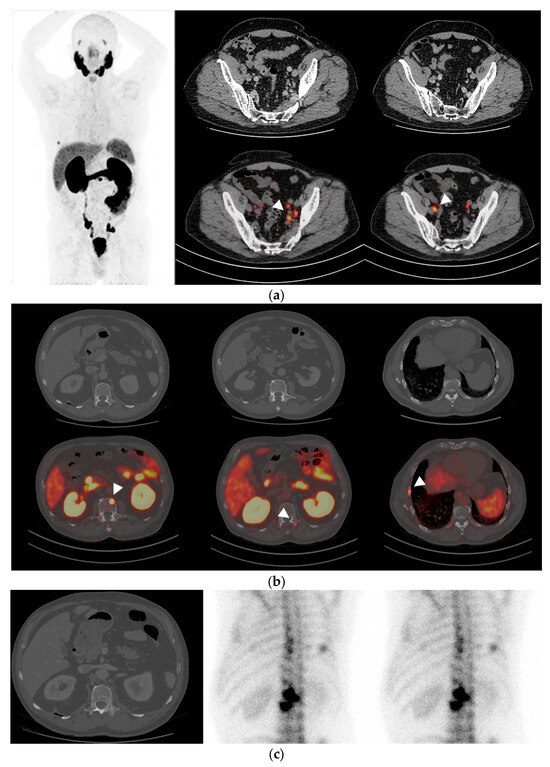

3.2. PSMA-PET/TC Findings

3.3. Comparative Performance of PSMA-PET/CT and CT

3.4. Comparative Performance of Bone Scintigraphy and PSMA-PET/CT

3.5. Comparative Performance of PSMA-PET/CT and Conventional Imaging